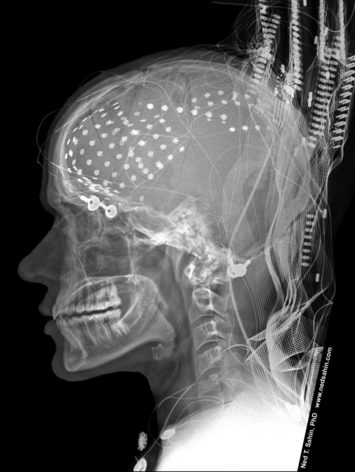

The lighting design is crafted by the observers themselves. Prior to the performance, five paintings with varying emotional effects were selected and reactions were tested using the Muse - BCI device. We enlisted famous masterpieces to select colors corresponding to the emotions experienced. Subsequently, these colors were incorporated into an AI system. With these colors, our audience can express their emotions through colors, thereby creating lighting projections on the screen.

This work offers individuals the opportunity to observe their emotions in real-time. The neuro interface Muse records and measures the intricate electrical processes occurring in the human brain, capturing the expression of emotional states.

Focusing on Paul Ekman's list of primary emotions, four were selected for visualization: joy, anger, sadness, and pleasure. Following Robert Plutchik's Wheel of Emotions, each emotion corresponds to a color: joy is represented by yellow, anger by red, sadness by blue, and pleasure by purple.

During the installation, the color palette of emotional impulses is displayed on the screen, along with overall statistics indicating the percentage of each emotion. Additionally, through Kinect technology, these emotions are tracked to specific areas of the human body.